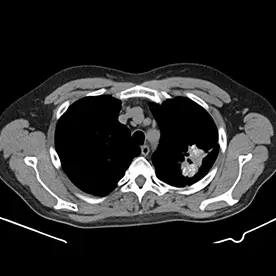

In der angefertigten CT des Thorax und Abdomens zeigen sich zwei große Lungenherde mit teils diffusen Verkalkungen und kleinen Kavernenbildungen im apikalen Ober- und Unterlappen links (Bild 1 und 2). Da es sich um eine ausgeheilte Infektion zu handeln scheint, kann man hier von einem Simon-Spitzenherd sprechen.